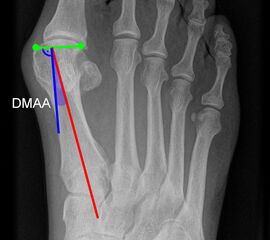

Gelenkflächenwinkel

DMAA (Distal metatarsal artikular angle, Syn. Gelenkflächenwinkel): Winkel zwischen der Achse des Os metatarsale I (rot) und dem Lot auf die distale Gelenkflächenebene (blau) des Os metatarsale I. Die Gelenkflächenebene (grün) wird definiert durch zwei Punkte, welche die mediale und laterale Begrenzung der Gelenkfläche definieren (Norm: <10° 5). Die Projektion des DMAA ist stark abhängig von der Rotation des Os metatarsale I 7. Daher ist bei der operativen Behandlung des Hallux valgus eine Beurteilung häufig erst nach Korrektur der Pronationsstellung des Os metatarsale I möglich. Tendenziell wird der DMAA auf präoperativen Röntgenaufnahmen überschätzt.